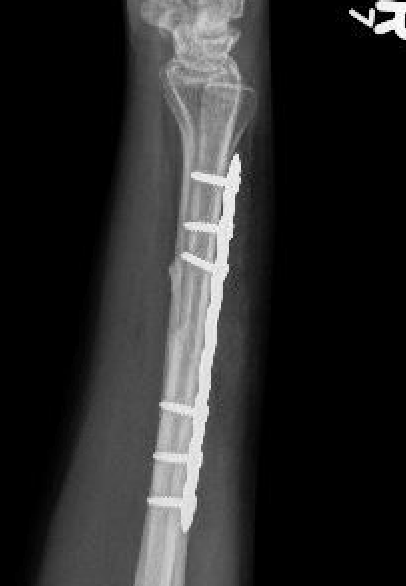

Operative management

Indications

- midshaft ulna fractures - higher risk of nonunion

Nonunions

Options

Compression plating

Intra-medullary nail

Ulna nonunion after plating